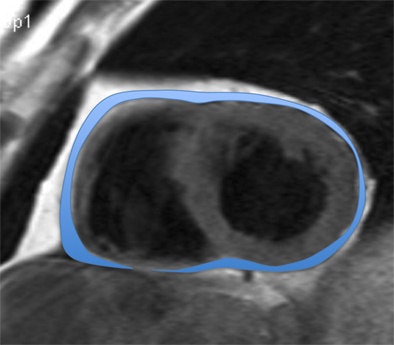

ECG-gated T1-weighted dark blood turbo spin-echo sequences were acquired in short- and long-axis views on a 1.5-tesla system (Siemens Healthcare). The study team quantified epicardial and paracardial adipose tissue between the atrioventricular plane and the apex using QMass 71 software (Medis).

The results, adjusted for age and body mass index (BMI), showed that patients with chronic MDD had significantly increased mean EAT volumes (92 ± 7 mL) compared with controls at 69 ± 5 mL (p = 0.016) and patients with recurrent MDD at 66 ± 5 mL (p = 0.006).

"EAT was significantly higher in patients with chronic MDD compared with controls and also compared with recurrent MDD," Hüper said. "The highest volume in the depressive group was 246 mL."